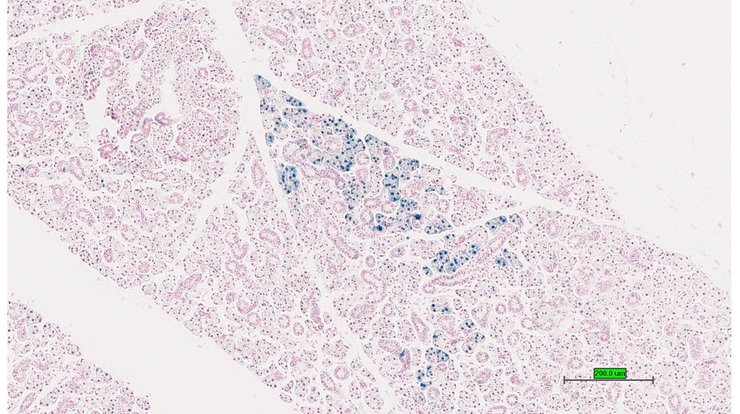

TS28: metanephros Present UC Davis_1880934 kidney

TS28: metanephros Present UC Davis_1880935 kidney

TS28: metanephros Present UC Davis_1880936 kidney

TS28: metanephros Present UC Davis_1881008 kidney

TS28: metanephros Present UC Davis_1881009 kidney

TS28: metanephros Present UC Davis_1881010 kidney